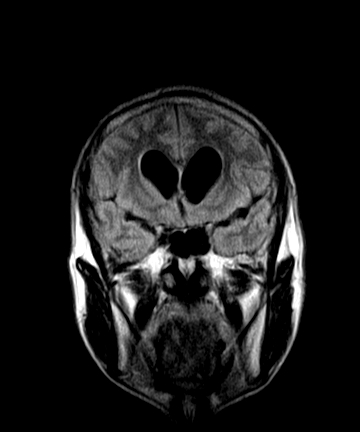

标题: MRI2064:少见病例。男性52,视力下降多年。 [打印本页]

标题: MRI2064:少见病例。男性52,视力下降多年。

考虑第四脑室室管膜瘤并梗阻性脑积水;部分性空蝶鞍;左侧上颌窦粘膜下囊肿。

加左上颌窦囊肿

1、四脑室肿瘤并并脑积水。考虑室管膜瘤可能性大,脑膜瘤等排。

2、左侧上颌窦及蝶窦囊肿。